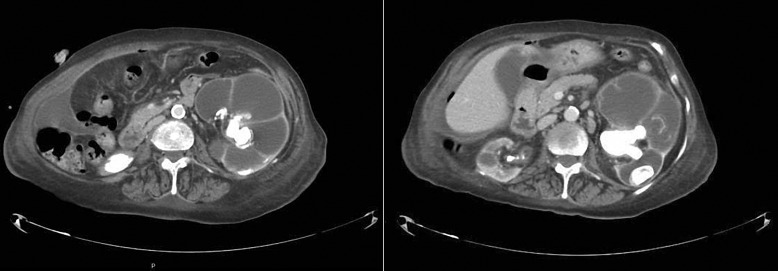

Case presentation: We present the clinical case of a 74-year-old woman, with a history of recurrent urinary tract infections associated with nephrolithiasis and stage 5D chronic kidney disease, on a PD program. The patient presented a non-specific 3-month state of progressive asthenia, with increased inflammatory parameters in the analytical controls. After presenting multiple negative urine cultures and peritoneal fluid cultures, she was hospitalized to study the constitutional syndrome. The imaging test revealed bilateral staghorn lithiasis with severe dilatation of the right renal pelvis and great cortical thinning. Given the suspicion of XGP, it was decided to perform right renal nephrectomy, which was confirmed after the anatomopathological study. Prior to the intervention, she was transferred to hemodialysis. Over the following months, significant clinical and analytical improvement was observed.